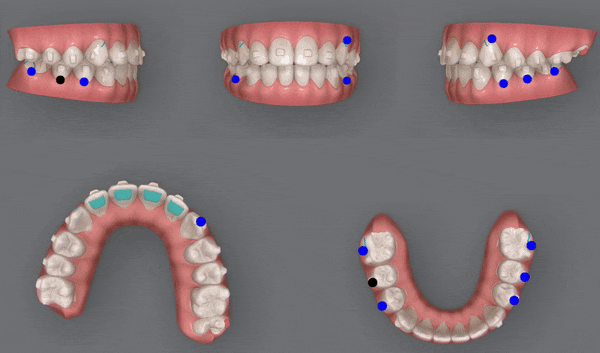

1st (40개)

첫번째 클린체크의 영상입니다.

인비절라인의 장점 중의 하나는

교정 후의 모습을 예측할 수 있는것 입니다.

원장님께서 클린체크 디자인을 마치게 되면

인비절라인 교정치료 후에

치아이동이 어떻게 변화하는지 클린체크를 통해 확인 해 볼 수 있는것인데요.

클린체크대로

치아들이 움직이면서 점점 가지런해 지는게 보이시나요?

첫번째 클린체크에서는 총 40개의 장치로

진행 해드렸습니다.

청소년인비절라인

유펜바른치과에서

인비절라인 단 40개의 장치로

악궁이 확장되면서 뻐드러져 있던 송곳니가 제 위치를 찾으며

자리를 잡아 가지런해졌습니다.